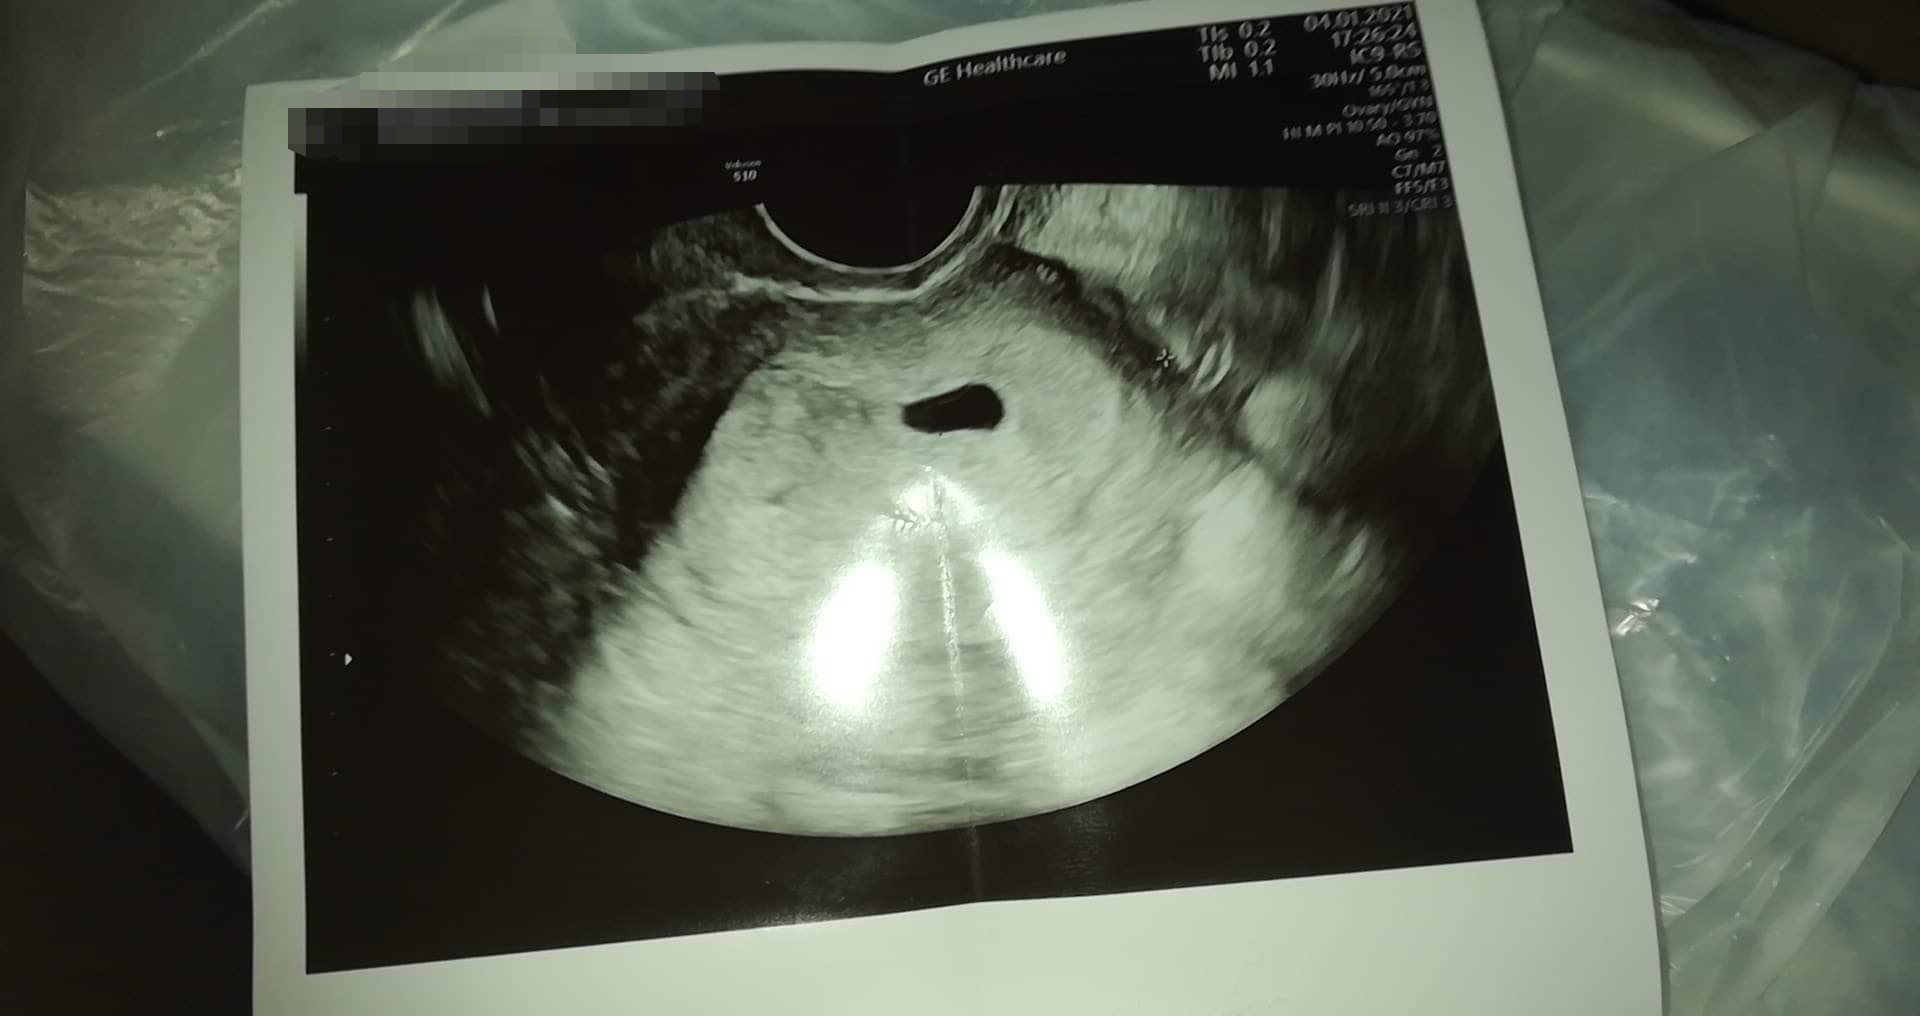

Wygląda jakby lekarz nie sprawdził wymiarów albo sprawdził przed zdjęciem... U mnie na zdjęciu na jednym końcu pęcherzyka i na drugim jest taki krzyżyk jak u Ciebie po prawej stronie pęcherzyka, a między tym kreska przez środek pęcherzyka - w ten sposób lekarz zmierzył pęcherzyk. Wstawiam zdjęcie, żebyś zobaczyła o co mi chodzi 😊